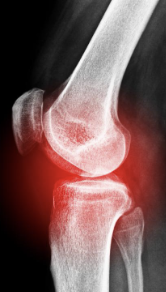

무릎 관절염 증상 원인 치료방법 등 무릎 관절염과 관련된 정보를 알아보도록 하겠습니다. 무릎 관절염은 무릎 관절의 연골 파괴, 염증 및 변형으로 인해 발생하는 질환입니다. 증상으로는 통증, 감각 이상, 충동성 통증, 강직성 및 관절의 이상운동이 포함된다. 주요 위험 인자로는 노화, 비만, 골관절염, 부상 및 과도한 사용 등이 있습니다. 진단은 증상 및 영상진단 검사를 통해 이루어지며, 치료는 수술, 약물 치료, 생활습관 변화, 물리 치료 등이 있습니다. 무릎 관절염은 진행성이며, 조기 발견 및 치료가 중요합니다. 예방을 위해서는 체중 조절, 적극적인 운동, 관절 보호를 위한 적절한 신발 착용 등이 필요합니다.

무릎 관절염 증상에 대해 알아보겠습니다. 무릎 관절염은 무릎 관절에 염증이 생기는 질환으로, 통증, 부종, 강직, 운동 제한 등의 증상을 유발합니다. 무릎 관절염은 여러 가지 원인에 의해 발생할 수 있으며, 나이가 들면서 관절의 손상이 증가하므로 노인층에서 많이 발생하는 질환입니다. 하지만 젊은 층에서도 과도한 운동, 스포츠 부상, 비만 등으로 인해 무릎 관절염을 앓는 경우가 있습니다.